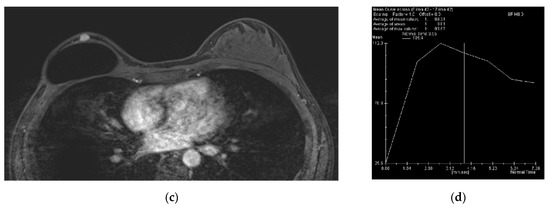

The Usefulness of Magnetic Resonance Imaging (MRI) for the Detection of Local Recurrence after Mastectomy with Reconstructive Surgery in Breast Cancer Patients